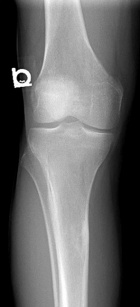

43 y/o male w 5 years of chronic R knee pain, worsening over the past 3 years. Feels like “crunching marbles”. Pain at night and worse with activity. No weight loss, fevers/chills. No systemic complaints.

PE: R knee effusion; crepitus, palpable masses near popliteal fossa, mild dec R knee ROM secondary to pain, neurovascularly intact, 5/5 motor.

Zoom image: Radiological image Radiological image.